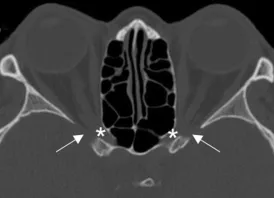

Axial CT of foramen rotundum (asterisks).

Foramen Ovale